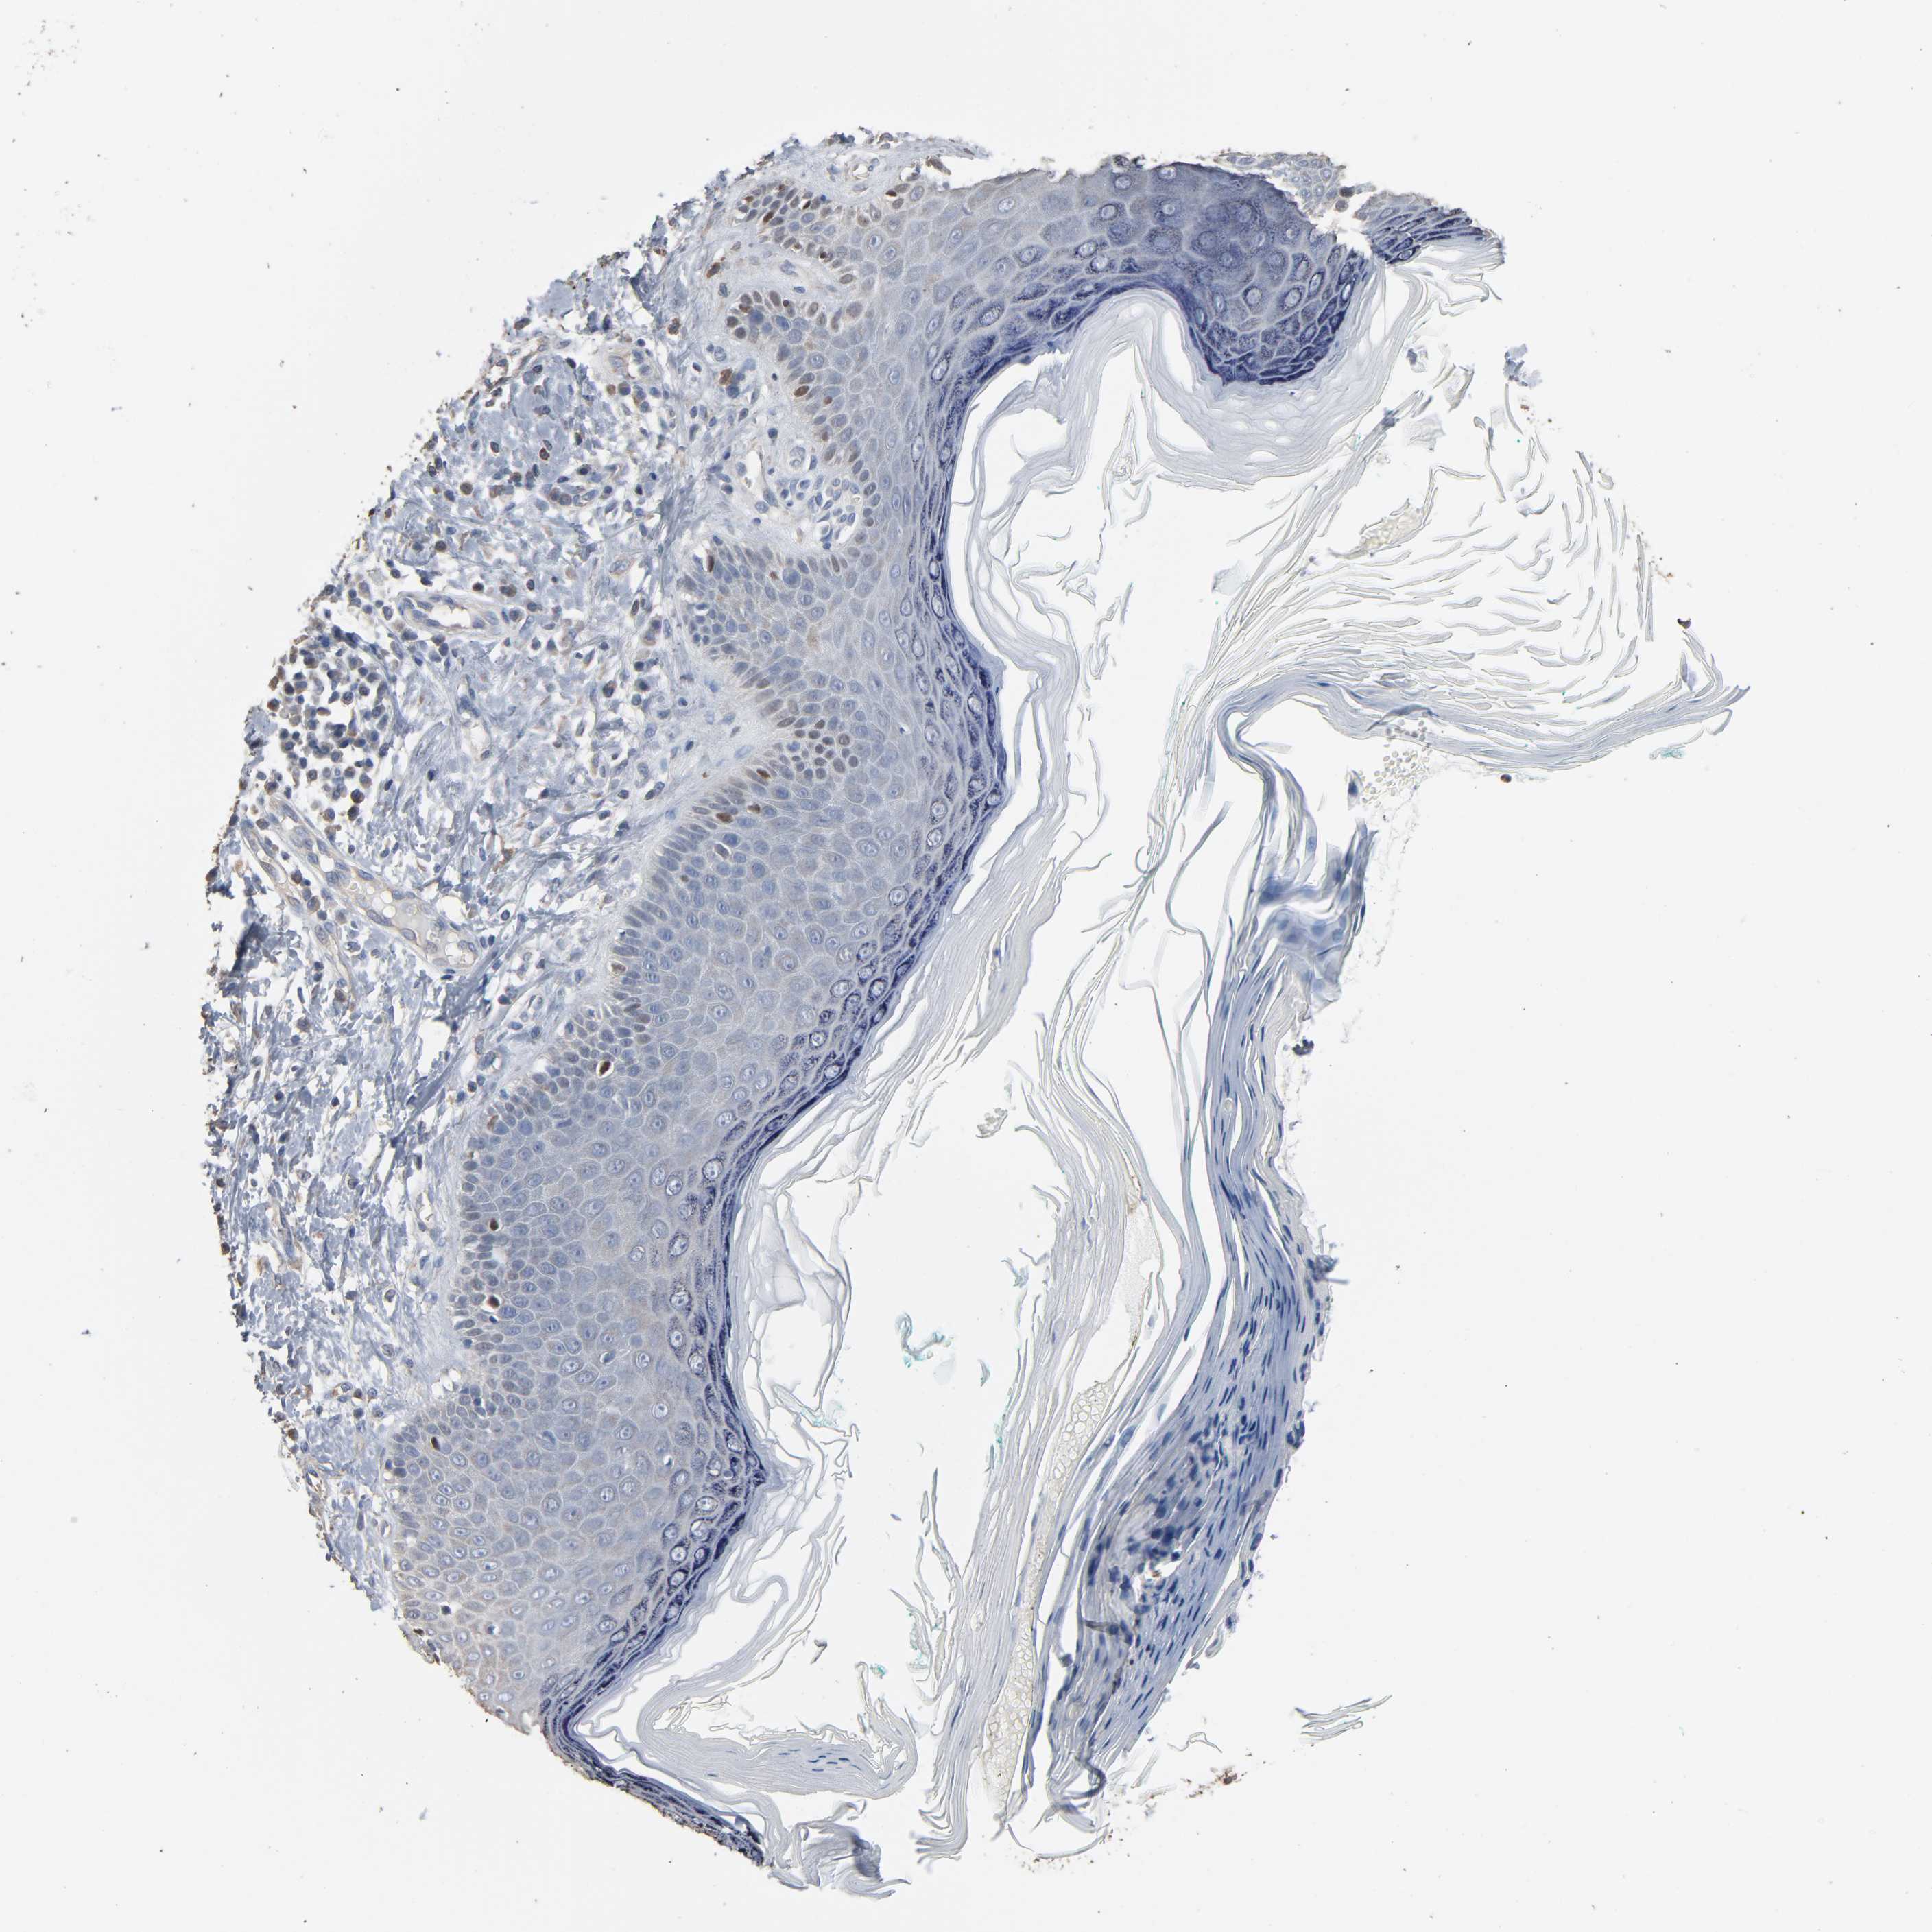

Basal cell and squamous cell cancer

SKIN CANCER - Protein expressioni

A mouse-over function shows sample information and annotation data. Click on an image to view it in a full screen mode. Samples can be filtered based on level of antibody staining by selecting one or several of the following categories: high, medium, low and not detected. The assay and annotation is described here.

Antibody stainingi

Antibody staining in the annotated cell types in the current human tissue is reported as not detected, low, medium, or high, based on conventional immunohistochemistry profiling in selected tissues. This score is based on the combination of the staining intensity and fraction of stained cells.

Each image is clickable and will lead to virtual microscopy that enables deeper exploration of all samples and also displays staining intensity scores, fraction scores and subcellular localization as well as patient and tissue information for each sample.

Antibody HPA001923

Antibody HPA003908

Staining

High

Medium

Low

Not detected

Intensity

Strong

Moderate

Weak

Negative

Quantity

>75%

75%-25%

<25%

None

Location

Nuclear

Cytoplasmic/membranous

Cytoplasmic/membranous,nuclear

Squamous cell carcinoma, NOS

Basal cell carcinoma